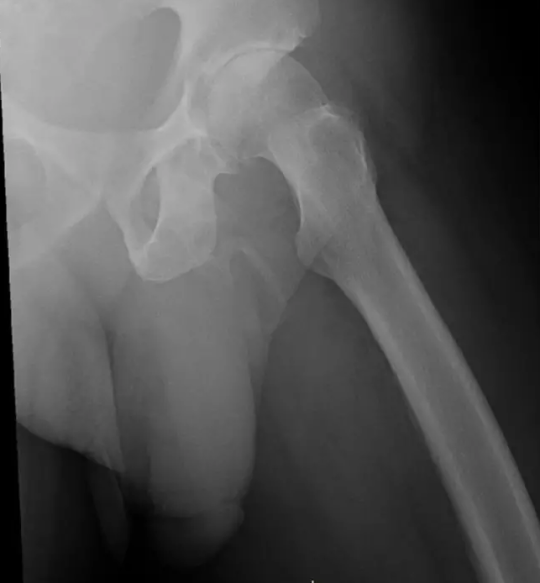

Hình ảnh chụp X-quang cho thấy xương chậu không bị vỡ nhưng lại thấy các tế bào xương hình thành trong dương vật của người đàn ông này, được gọi là dương vật “hóa thạch”.

Kết quả cho thấy vùng xương chậu của ông ra hoàn toàn bình thường, không hề có dấu hiệu nứt vỡ, thay vào đó, các bác sĩ lại phát hiện ra các tế bào xương đang hình thành trong dương vật của người đàn ông này khiến nó đang dần "hoá thạch".

Sau khi xem xét tình hình thực tế, các bác sĩ chẩn đoán anh ta bị "hóa thạch"dương vật - sự hình thành xương bất thường xảy ra khi các mô mềm bình thường bị vôi hóa và cứng lại, nhưng có vẻ người đàn ông 63 tuổi này không thích những gì mình được nghe thấy nên rời khỏi bệnh viện và bỏ qua lời khuyên của bác sĩ.